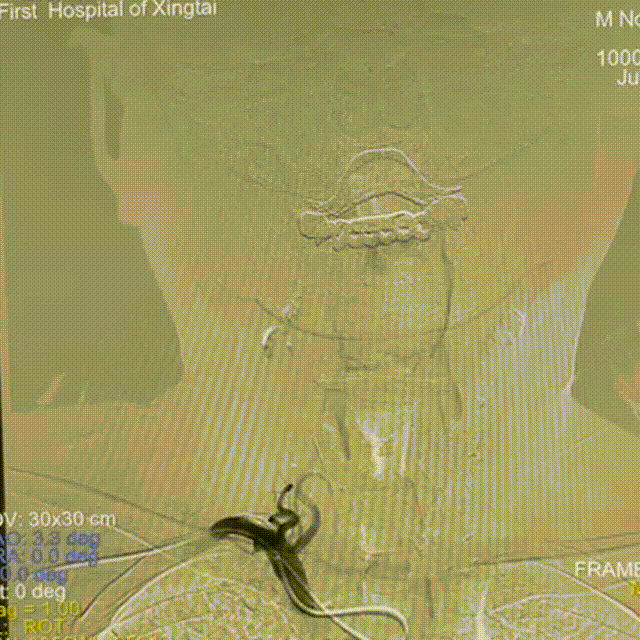

冠脉球囊辅助下,Locaste 088长鞘通过狭窄段。

动脉长鞘怎么置入【有励可说】Locaste 088长鞘经左桡治疗左侧锁骨下动脉狭窄一例_https://www.jmylbn.com_新闻资讯_第11张

支架通过Locaste 088长鞘到达狭窄段。